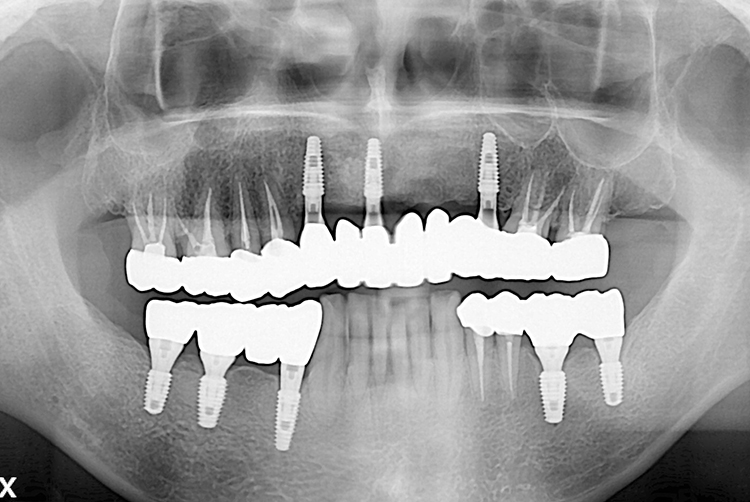

PX20190216_113435_0198_00000000.jpg

치료후 : 2019-02-16

세종치과는 많은 환자와 다양한 케이스를 바탕으로 항상 편안한 임플란트 수술을 제공하고자 노력하고,

오래동안 튼튼히 쓸 수 있는 임플란트 수술을 가장 큰 목표로 삼고 있습니다